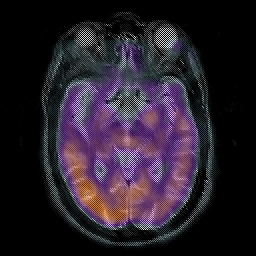

Subacute Stroke overlay -- Slice #10

[Home][Help][Clinical] Slice 10